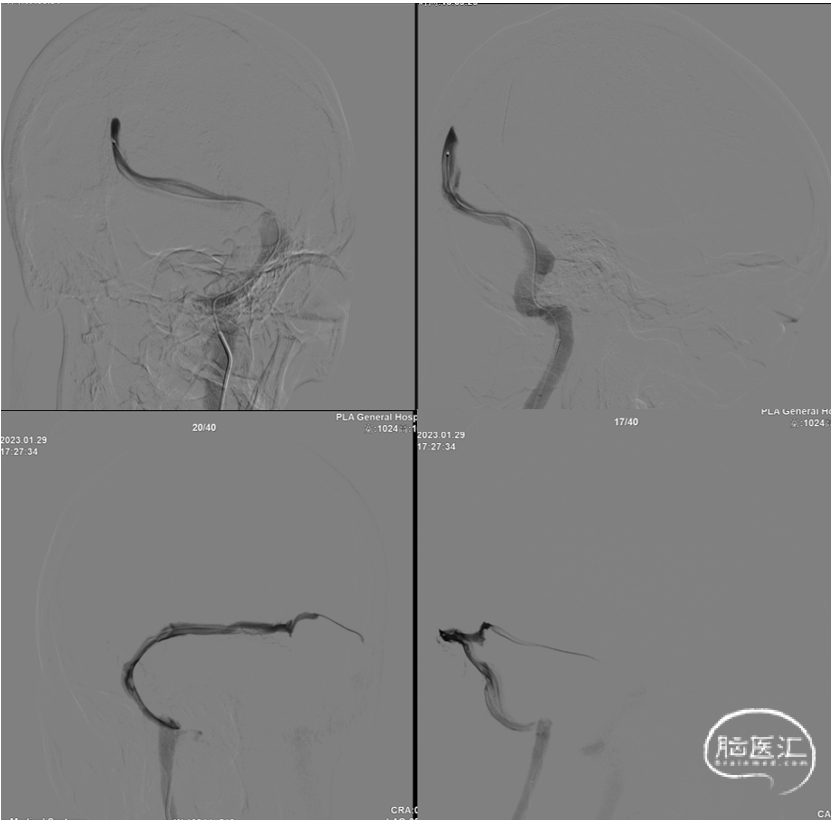

全脑血管造影动脉期、毛细血管期造影无明显异常。静脉期:右侧横窦、乙状窦纤细,左侧横窦、乙状窦交界区重度充盈缺损。

图3.右侧颈内动脉造影